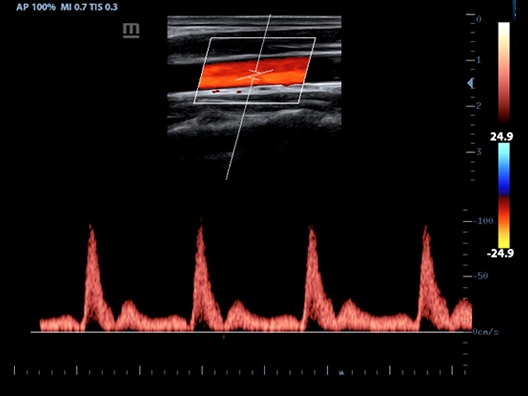

Клинические изображения

- Режимы сканирования: B/M/Color Dopler/Color M/Power/Directional Power Doppler Flow Imaging

- PW Doppler, включая HPRF (High Pulsed Repitition Frequency)